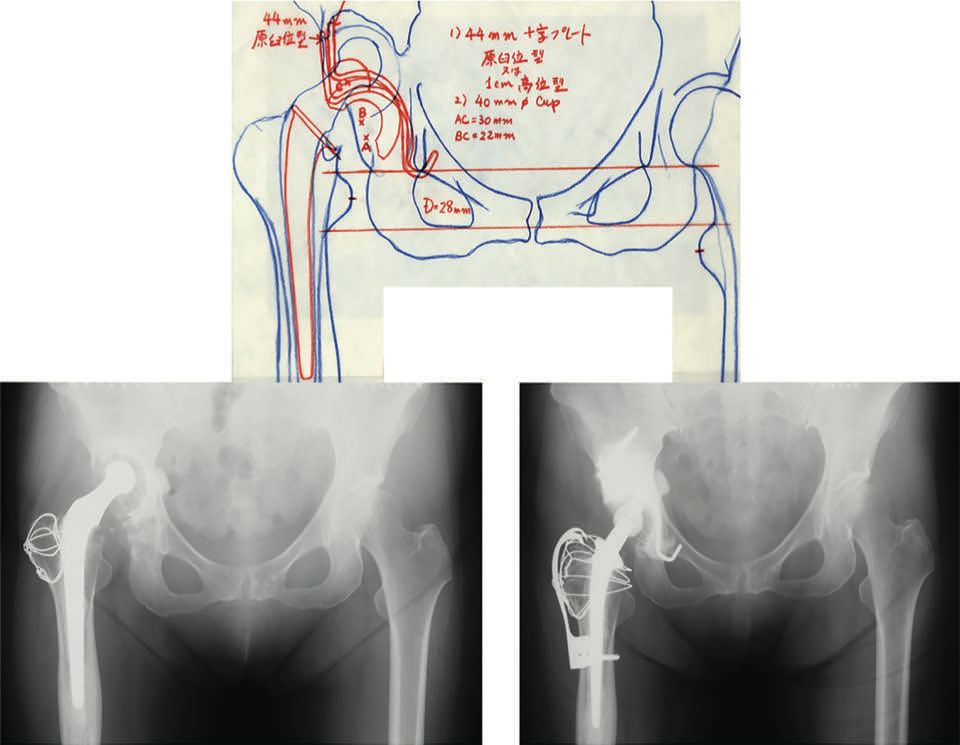

Preoperative planning is usually performed using software and scanned images in order to produce a 3D model (Kyocera) (Fig. 5).

The anterior-posterior diameter of the acetabulum determines the size of the KT cross. A pitfall to avoid is choosing a plate that is too large based solely on AP x-ray images. As shown in Case 1, the correct size and shape of the structural allograft can be estimated in advance, and the surgeon can determine the spatial relationship between the anatomical markers and the KT cross (Fig. 6).

This works as a guidance system. In Case 2, the medial wall and acetabular notch have been destroyed.

The medial wall, acetabular notch and weight-bearing zone need to be reconstructed. An angioscan can help avoid vascular complications by showing the acetabular markers and the vascularisation in the event of protrusion.